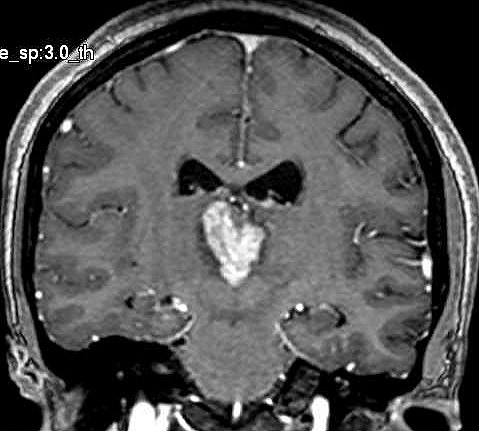

| Fem. 17a. |

| Nódulo sólido homogêneo preenchendo o III ventrículo, com limites precisos, com hipossinal em T1 e hipersinal em T2 e FLAIR, que se impregna por contraste paramagnético. Lesão menor implantada no assoalho do IV ventrículo provavelmente representa disseminação por via liquórica. |

| CORONAL, T2 | T1 COM CONTRASTE | |

| F. 17a. Tumor teratóide rabdóide atípico de III ventrículo. RM | HE | VIM, GFAP | HHF35, desmina, 1A4 | AE1AE3, EMA |